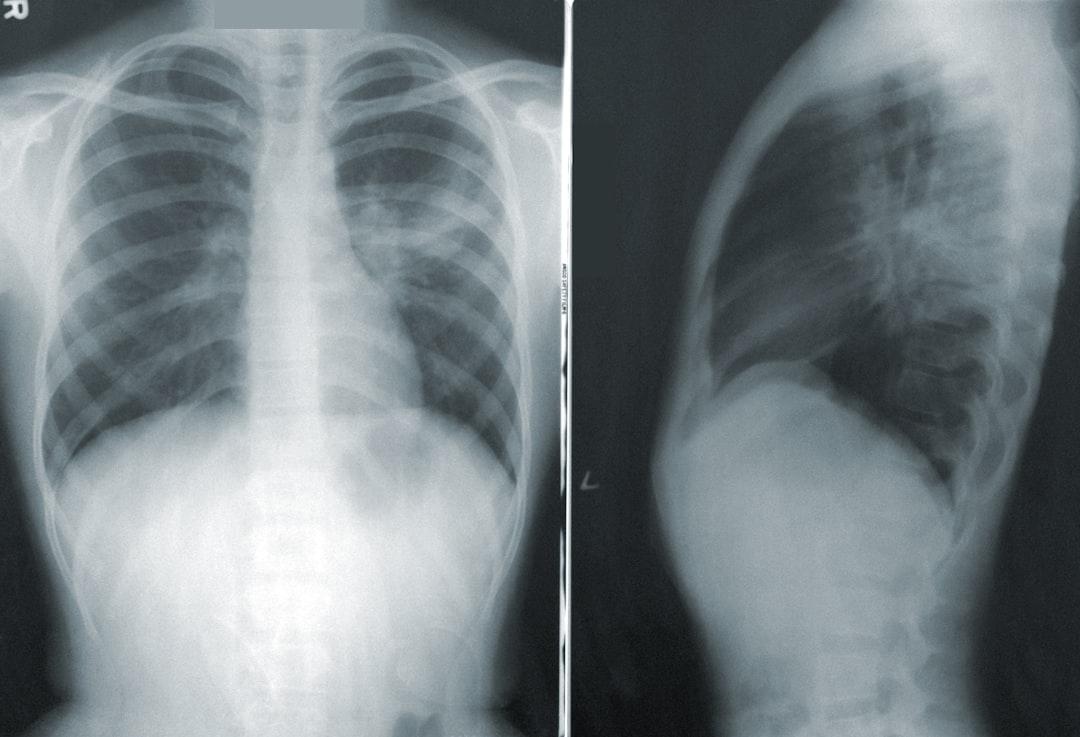

Diagnosen ställs genom läkarundersökning, där lungor lyssnas på och allmäntillstånd bedöms. Vid behov görs en utredning som kan inkludera blodprov, såsom CRP, lungröntgen eller sputumprov för att utesluta andra sjukdomar. Studier som visar på värdet av dessa diagnostiska metoder finns, men resultaten kan variera. Andra luftvägsinfektioner, såsom lunginflammation, kan ha liknande symtom som akut bronkit men innebär oftast ett allvarligare allmäntillstånd. Kom ihåg att det är alltid bäst att kolla med en läkare först för en korrekt diagnos. Kolla även med 1177 för mer information.